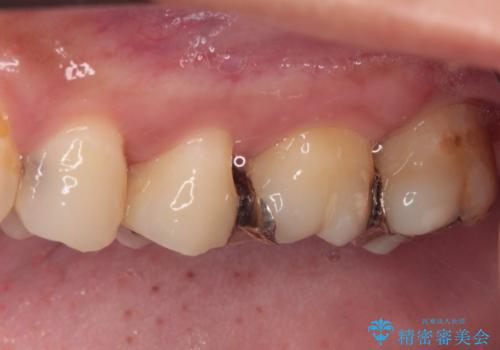

- 奥歯に頻繁に物が挟まるとのことで来院された患者様です。

最近ものが挟まりやすくなったり、冷たいものがしみるようになったりといった症状があり、診査したところ、むし歯や歯質の欠損、不適修復物などが認められました。

処置を行った歯以外にもむし歯と思われる歯が多数ありますが、費用のかかる治療であれば、優先順位をつけて、処置を急ぐ歯から処置を進めて行きました。